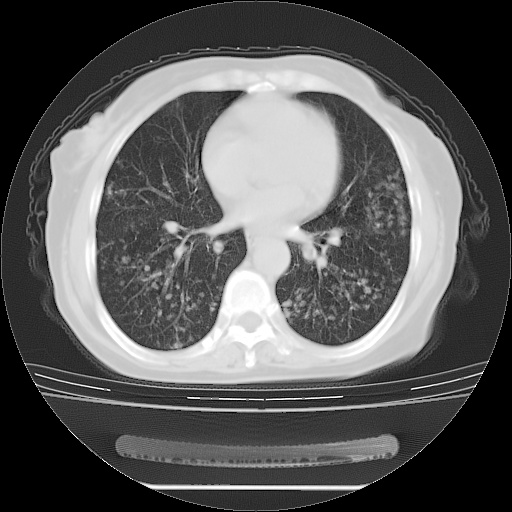

患者女性,72岁,慢性咳嗽3月余,曾抗炎治疗无效果,最近抗结核治疗约半月余,症状缓解。

ct示两肺粟粒状病灶,以两肺上叶尖后段及下叶背段分布为主;首先考虑结核。请战友们分析。

考虑 1 弥漫性泛细支气管炎, 2 结核不除外/.  有小叶中心结节 和 树芽征!!

两肺内病灶呈小结节状和树芽状,纵膈的肿大的淋巴结密度不均匀,并见有钙化,考虑为两肺结核可能更大些。

两肺内病灶呈小结节状和树芽状,纵膈的肿大的淋巴结密度不均匀,并见有钙化,多形态病灶,考虑为两肺结核,肝内考虑小囊肿。